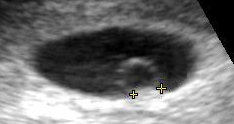

A gestational sac can be reliably seen on transvaginal ultrasound by 5 weeks' gestational age (approximately 3 weeks after ovulation). The embryo should be seen by the time the gestational sac measures 25 mm, about five-and-a-half weeks.[10] The heartbeat is usually seen on transvaginal ultrasound by the time the embryo measures 5 mm, but may not be visible until the embryo reaches 19 mm, around 7 weeks' gestational age.[5][11][12] Coincidentally, most miscarriages also happen by 7 weeks' gestation. The rate of miscarriage, especially threatened miscarriage, drops significantly after normal heartbeat is detected, and after 13 weeks.[13]

Contents in the cavity of the uterus seen at approximately 5 weeks of gestational age

Artificially colored, showing gestational sac, yolk sac and embryo (measuring 3 mm as the distance between the + signs)